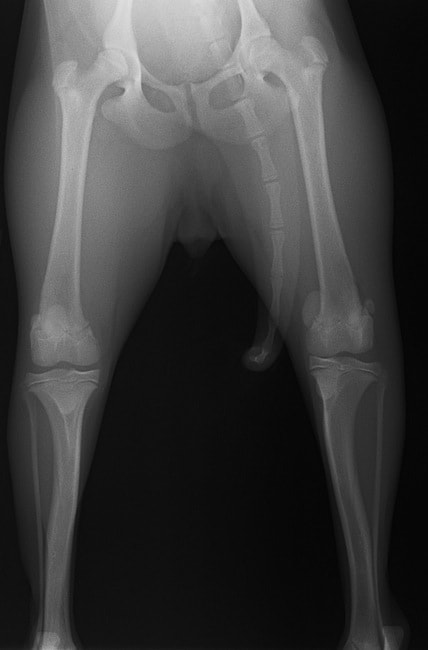

■ 症例20 ポメラニアン 8ヶ月 1.8kg

左右膝蓋骨脱臼 グレードⅢ

2ヶ月前から間欠的跛行が認められ、両膝の膝蓋骨脱臼整復術を行った。

手技は縫工筋及び内側広筋の解放、脛骨粗面の外側転位、滑車ブロック形造溝術、内外側関節包の縫縮を選択し実施した。

右側の膝蓋骨脱臼は上記手技で整復されたものの、左側はそれのみでは膝蓋骨が浮く様子が認められた。その為、PDS縫合糸にて膝蓋靱帯を1糸のみ縫合し、靱帯の縫縮を行った。

膝蓋骨脱臼は膝関節における膝蓋骨の内外側の脱臼と定義されるが、時として単純な内外の脱臼ではなく、膝蓋骨が大きく前方に浮き上がるように脱臼する場合がある。特にトイプードルやポメラニアンといった犬種に多く認められる。

内側脱臼に加えて前方への浮き上がりを矯正する為に、従来より脛骨粗面転移により膝蓋靭帯を外方と下方に引っ張り、固定する方法を選択する。膝蓋骨の前方への浮き上がりが軽度の場合は、従来法ではなく関節包の縫縮で対応していた。しかし、一部の症例で膝蓋骨の動きが悪くなり伸展機構が円滑に機能せずロボット様歩行になるケースがあった。

その為、膝蓋靭帯自体を縫縮する方法を採用した。この方法により、膝関節の伸展機構を妨げず膝蓋骨の軽度の浮きを矯正することが可能となった。

本症例の経過は良好である